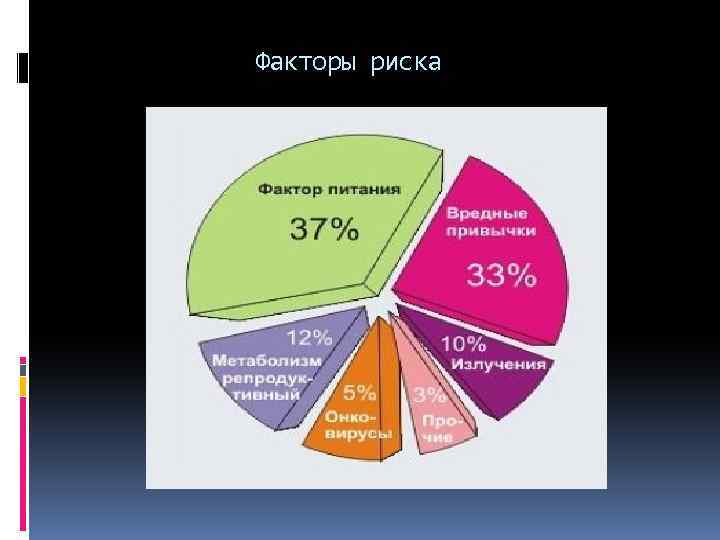

Факторы риска